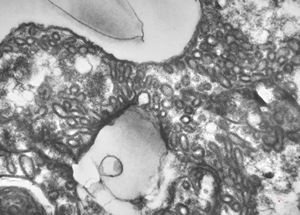

M,33y. | cryptosporidiosis - duodenum, im | munodeficient pacient